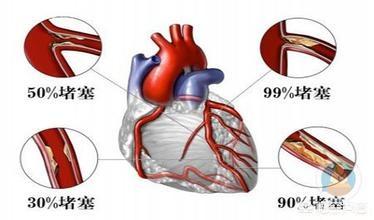

M. Zhu, 47 ans, s'est inquiété lorsqu'un cardiogramme a révélé une sténose de 70 % il y a un an.

Sous les conseils du médecin, en suivant le traitement pendant un an et en menant une vie saine, une récente imagerie de contrôle a montré que la sténose de ce vaisseau sanguin s'était améliorée et n'était plus que de 50 %.

La plaque la plus grave est la plaque cardiovasculaire, ou plaque carotidienne, dont l'aggravation entraîne une ischémie myocardique, une ischémie cérébrale ; si elle n'est pas activement contrôlée, la plaque peut même se rompre et se thromboser, entraînant un infarctus du myocarde ou un infarctus cérébral.

La plaque carotidienne peut être temporairement observée sans médicament si elle est inférieure à 50 % et si le LDL n'est pas élevé ; si la sténose de l'artère carotide est supérieure à 50 % ou si la plaque est molle, il est nécessaire de prendre des statines pour contrôler la plaque. La plaque cardiovasculaire doit également être traitée par statine pour éviter son aggravation. Il est également nécessaire de contrôler activement le diabète, l'hypertension et l'hyperlipidémie, et le LDL devrait idéalement être inférieur à 2,6, voire réduit à moins de 1,8 pour plus de sécurité.

L'athérosclérose est fréquente à 80 % chez les personnes de plus de 50 ans, et l'incidence des plaques carotidiennes augmente avec l'âge. Chez quelques personnes âgées, les plaques conduisent à une sténose, qui peut entraîner des changements hémodynamiques et même une obstruction.

L'incidence des plaques a augmenté de manière significative chez les patients âgés de plus de 60 ans par rapport aux patients âgés de 50 à 59 ans, alors que la différence d'incidence des plaques chez les patients âgés de plus de 60 ans était faible, ce qui indique que l'incidence des plaques a augmenté de manière significative chez les personnes âgées par rapport aux personnes d'âge moyen.

Il est important de noter queLes patients atteints de plaques artérielles qui présentent un rétrécissement de 50 % des artères ou une formation de plaques instables, en particulier dans les artères coronaires, de la tête et du cou, doivent recevoir un traitement par statines en association avec de l'aspirine. L'association de la statine pour rétrécir et stabiliser la plaque et de l'aspirine pour prévenir la thrombose au niveau de l'endothélium rompu réduit considérablement le risque d'événements cardiovasculaires, ce qui en fait une combinaison classique et un médicament de base pour le traitement des plaques artérielles et la prévention des événements cardiovasculaires et cérébrovasculaires.